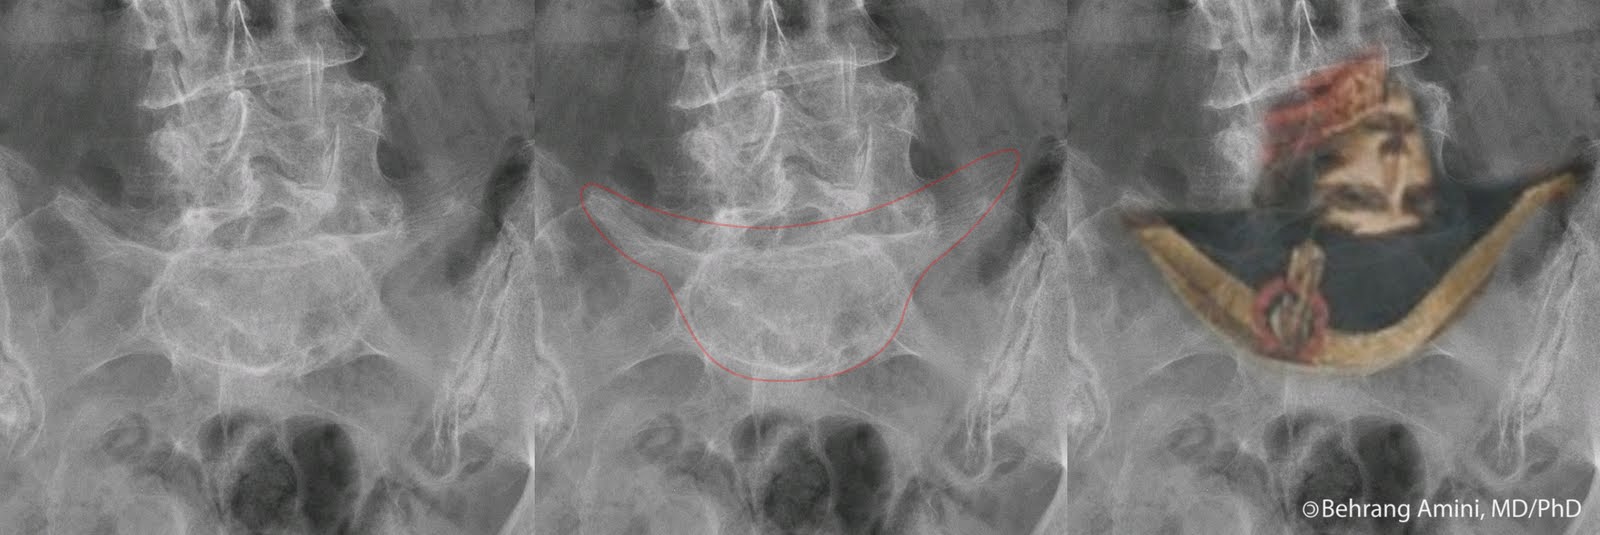

The images above are from a patient with POEMS syndrome. We see sclerotic lesions in the humerus, pelvis, and proximal femur, some of which have the typical ring-like appearance (e.g., the left intertrochanteric region). Looking through our 20 or so cases of POEMS here, I wasn't able to find any with the pathognomonic proliferative changes described by Resnick, so a look at the original paper is worthwhile to get familiar with this appearance.